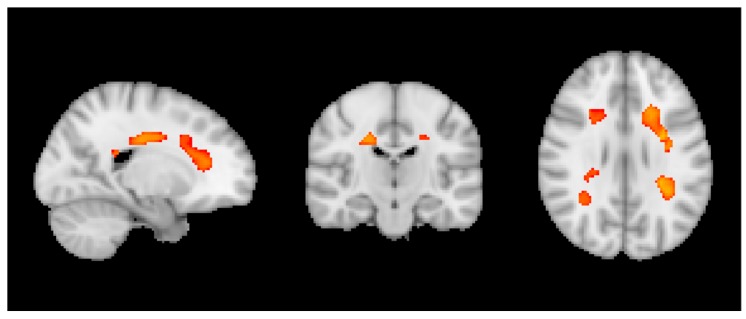

Across all participants, we observed a negative correlation in VBM with wine notably in bilateral deep white matter regions (Figure 1).

Figure 1.

Negative correlation between wine and VBM across all individuals. p < 0.05 TFCE corrected.

Moreover, we observed a negative correlation between VBM and caffeine only in sCON individuals notably in the white matter that was more pronounced in left parietal and right frontal regions (Figure 3).

Figure 3.

Negative correlation between caffeine and VBM for only sCON individuals. p < 0.05 TFCE corrected.

Concerning brain MRI, we first assessed the entire dataset of healthy elderly controls and observed a negative correlation between wine consumption and VBM in bilateral fronto-parietal white matter (WM). This result may appear contra-intuitive at first glance, as VBM is usually used to assess modifications in grey matter (GM) concentration. However, it should be noted that microvascular WM lesion are very frequent in the elderly population. They appear as hypersignal on T2w/FLAIR (fluid attenuated inversion recovery) sequences, and are usually reported on those sequences, e.g., using the Fazekas score. Although less evident and consequently usually less frequently assessed, those microvascular WM lesions also appear as a hypointense signal on T1w images, which is the basis of the VBM analysis. The negative correlation between wine and VBM in WM indicates less hypointense signal on T1 and consequently a reduced severity of WM lesions with increasing wine intake. Interestingly, the additionally performed TBSS analysis of the WM skeleton did not reveal significant differences in FA (fractional anisotropy), which is considered as a microstructural marker of axonal integrity. Taking together the results of VBM and TBSS, this indicates that increased wine intake may reduce microvascular lesions of the fronto-parietal WM, while association between this consumption and microstructural integrity of the WM seems more difficult to establish. Interestingly, an increasing number of studies point to the positive association between low to moderate wine consumption and WM integrity. In particular, Verbaten reported less white matter damage in elderly light and moderate drinkers [33]. Similar results were reported by Mukamal for elders consuming less than six units per week [69] for the vast majority of the present cases. Interestingly and unlike cognitive performances, we did not detect a negative association between heavy drinking and WM integrity. The absence of a U-shape association here may be related to the limited number of heavy drinkers in this sample and low exposure to cardiovascular risk factors due to the exclusion criteria.

A separate set of findings concerned with the association between consumption and brain structure as a function of the cognitive fate in this longitudinal series. We built regression models for each subgroup. Based on repeated neurocognitive testing, the healthy controls were sub-classified into sCON, iCON and dCON. It is important to emphasize that even for the dCON participants, the cognitive profile remains within the normal limits at follow-up, however, the individual cognitive profile slightly decreased two times at 18 and 36 months follow-up. In contrast, the cognitive profile remains constant twice for the sCON participants, and is intermediate for the iCON participants. Only in the sCON individuals, we observed a positive correlation between wine and ASL in the WM, overlapping with the regions of the VBM results across all participants reported above. This indicates that wine does not only reduce the WM lesion load, but also improves brain perfusion at baseline; however, this effect is limited in cases who remained cognitively stable over time. It is noteworthy that among sCON cases, only six cases corresponded to the classical definition of heavy drinking (≥8 units for women and 15 for men), the mean consumption being less than one unit/day. In the same line, we found a negative association between caffeine consumption and VBM only for sCON participants in the right frontal and left parietal WM regions, without a significant association with TBSS parameters. Similar to the argumentat above, this might indicate that caffeine reduces WM lesion load only in sCON participants, without having a significant effect on WM microstructural integrity. Interestingly, and in contrast to wine, most of the sCON cases were of moderate or heavy consumption of caffeine, not supporting the idea of a U-shaped association between caffeine consumption and WM lesions. Moreover, the positive association between caffeine consumption and cognition was present only in sCON participants consistent with the view that caffeine is a cognitive normalizer rather than a cognitive enhancer [70,71]. As for cognitive outcome, chocolate consumption was not associated with the MRI parameters studied in the present series suggesting that the chronic consumption of chocolate is not beneficial nor deleterious for brain integrity or cognitive performances in old age.